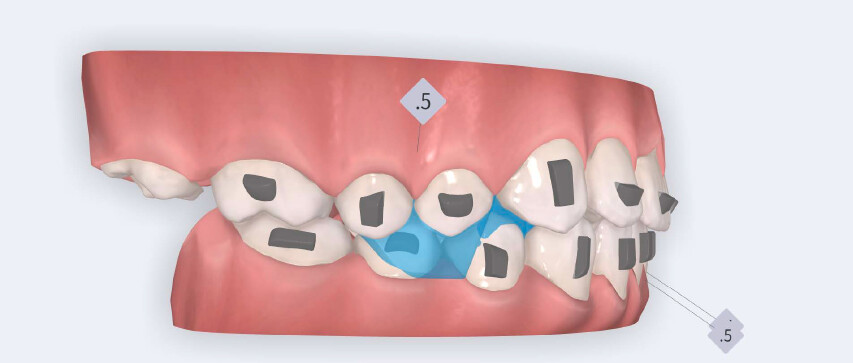

O tratamento seguiu o protocolo de avanço mandibular Angel Aligner A6, com o objetivo principal de alcançar a correção precoce da discrepância sagital enquanto abordava simultaneamente o alinhamento dentário e a coordenação transversal.

O plano de tratamento incluiu:

- Início do avanço mandibular a partir do 4.º alinhador utilizando blocos de avanço mandibular;

- Expansão da arcada para resolver o apinhamento e melhorar a coordenação transversal;

- Redução interproximal seletiva na região anterior mandibular para criar espaço e controlar a inclinação dos incisivos;

- Intrusão programada dos incisivos centrais superiores para reduzir a exposição gengival e corrigir o sorriso gengival;

- Intrusão dos incisivos e caninos mandibulares para nivelar a Curva de Spee;

- Utilização de elásticos de Classe II com Angel Buttons durante a fase de refinamento, para reforçar a mecânica sagital, introduzidos na fase de alinhadores adicionais.

O tratamento foi realizado utilizando alinhadores transparentes Angel Aligner, com estrita observância dos limites biológicos periodontais. Tanto a intrusão dos incisivos superiores quanto a expansão transversal foram cuidadosamente monotorizadas durante todo o processo para evitar qualquer comprometimento periodontal. O avanço mandibular foi iniciado diretamente a partir do 4.º alinhador, utilizando blocos de avanço, eliminando a necessidade de uma fase preliminar de pré-avanço. O paciente encontrava- se no estágio CS3 da maturação das vértebras cervicais, correspondente ao surto de crescimento pubertário, um período biologicamente favorável para o desenvolvimento condilar e adaptação esquelética. Foram utilizados um total de 35 alinhadores com blocos de avanço, seguidos por 10 alinhadores adicionais incorporando elásticos de Classe II nos Angel Buttons para finalizar rotações e alinhamento. Com trocas semanais dos alinhadores, a duração total do tratamento foi de aproximadamente 45 semanas (10 meses), em conformidade com o tempo biológico esperado para a remodelação condilar. Para a intrusão anterior mandibular, o Protocolo Frog combinado com a redução interproximal (IPR) permitiu o nivelamento completo da Curva de Spee.